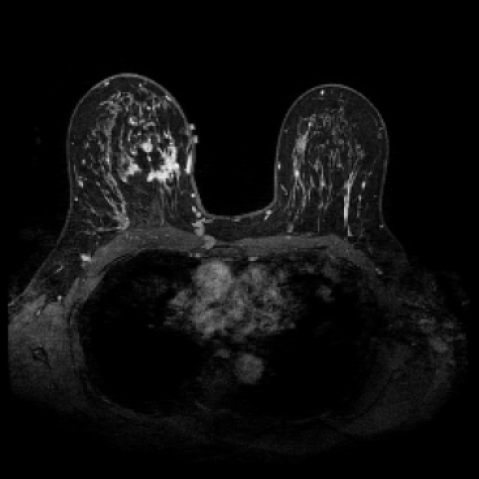

The goal of our research is not to generate fancy or visually appealing images, but rather to produce images that are useful for downstream tasks. Our focus is on creating synthetic data that have small domain gap with real data, helping to address the bottleneck of data scarcity in the field of machine learning for medical imaging. By generating images that are meaningful for specific tasks, we aim to improve the performance of models in clinical applications, ultimately driving advancements in medical image analysis where labeled data are often limited. In this experiment, We first train a 3D segmentation network using the images and the corresponding semantic maps from training set of the real Duke Breast dataset. The model and training details can be found in the Appendix B. The purpose is to allow the network to learn how to segment anatomical structures from real MRT data. After completing the training phase, we evaluated the segmentation network on four different datasets as shown in Table 2: (1) real images from the Duke Breast dataset training set, (2) real images from the Duke Breast dataset test set, (3) synthetic images generated by our SegGuidedDiff model [26] using semantic maps from the Duke Breast test set, and (4) synthetic images produced by our Med-LSDM model based on the same semantic maps. By evaluating the segmentation results on different real and synthetic images, we aim to investigate the effectiveness of the generative model in producing realistic images that could yield similar segmentation results to real data, suggesting that real and synthetic images lie in similar regions of the data distribution.

Table 2 presents the segmentation performance, measured by the Dice similarity coefficient averaged over all semantic classes, across different data sources. The real training data achieve the highest Dice score of 0.750, which indicates that the segmentation model achieves a 75% overlap between the predicted region and the ground truth. When tested on the real test set, the score falls slightly to 0.715, indicating good generalization.

In contrast, the segmentation result of synthetic data generated by SegGuidedDiff using 2D semantic map slices shows significantly lower performance (Dice = 0.602). Notably, SegGuidedDiff generates images slice-by-slice in 2D without modeling the full 3D spatial context. As a result, the synthesized volumes often suffer from inter-slice inconsistencies and unrealistic spatial structures, which negatively impact the downstream segmentation performance.

Our Med-LSDM-generated data, in contrast, achieves a Dice score of 0.70964, which is much higher than SegGuidedDiff and closely approaches the real data test performance. This indicates that our method’s 3D generation strategy successfully captures anatomical coherence across slices and produces realistic volumetric data. It is also important to note that the synthetic volumes are directly saved in NIfTI format without any post-processing, demonstrating the practical applicability and robustness of our framework.

The hypothesis of this experiment is that if the synthetic images generated by our model resemble real medical images in distribution, a segmentation network trained on real data should yield similar performance on synthetic data. By comparing the segmentation results across real and synthetic images, we can quantitatively assess the structural fidelity and semantic consistency of the generated data. The results confirm that segmentation performance on synthetic images is highly comparable to that on real images, indicating that our model successfully captures anatomically relevant structures. This suggests that synthetic data are not only realistic but also potentially beneficial as an augmentation strategy to improve segmentation tasks. Visualizations of the segmentation output are presented in Figure 6.